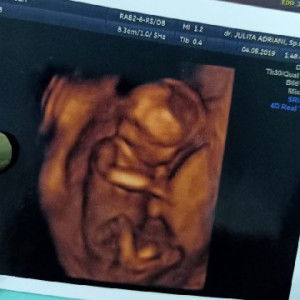

Hasil TP positif , tetapi Usg blm keliatan

Bun mau tanya dong kalo hasil TP seperti ini positif kah ? Tetapi di usg kok blm keliatan ya

Uk brp bulan bun? Kalo masih awal biasanya usg transvaginal bun biar terlihat atau tunggu 2-4mggu lagi yaa semoga sudah terlihat

Masih kecil bnget bun.. Mungkin ntr sbulan lgi udh keliatan